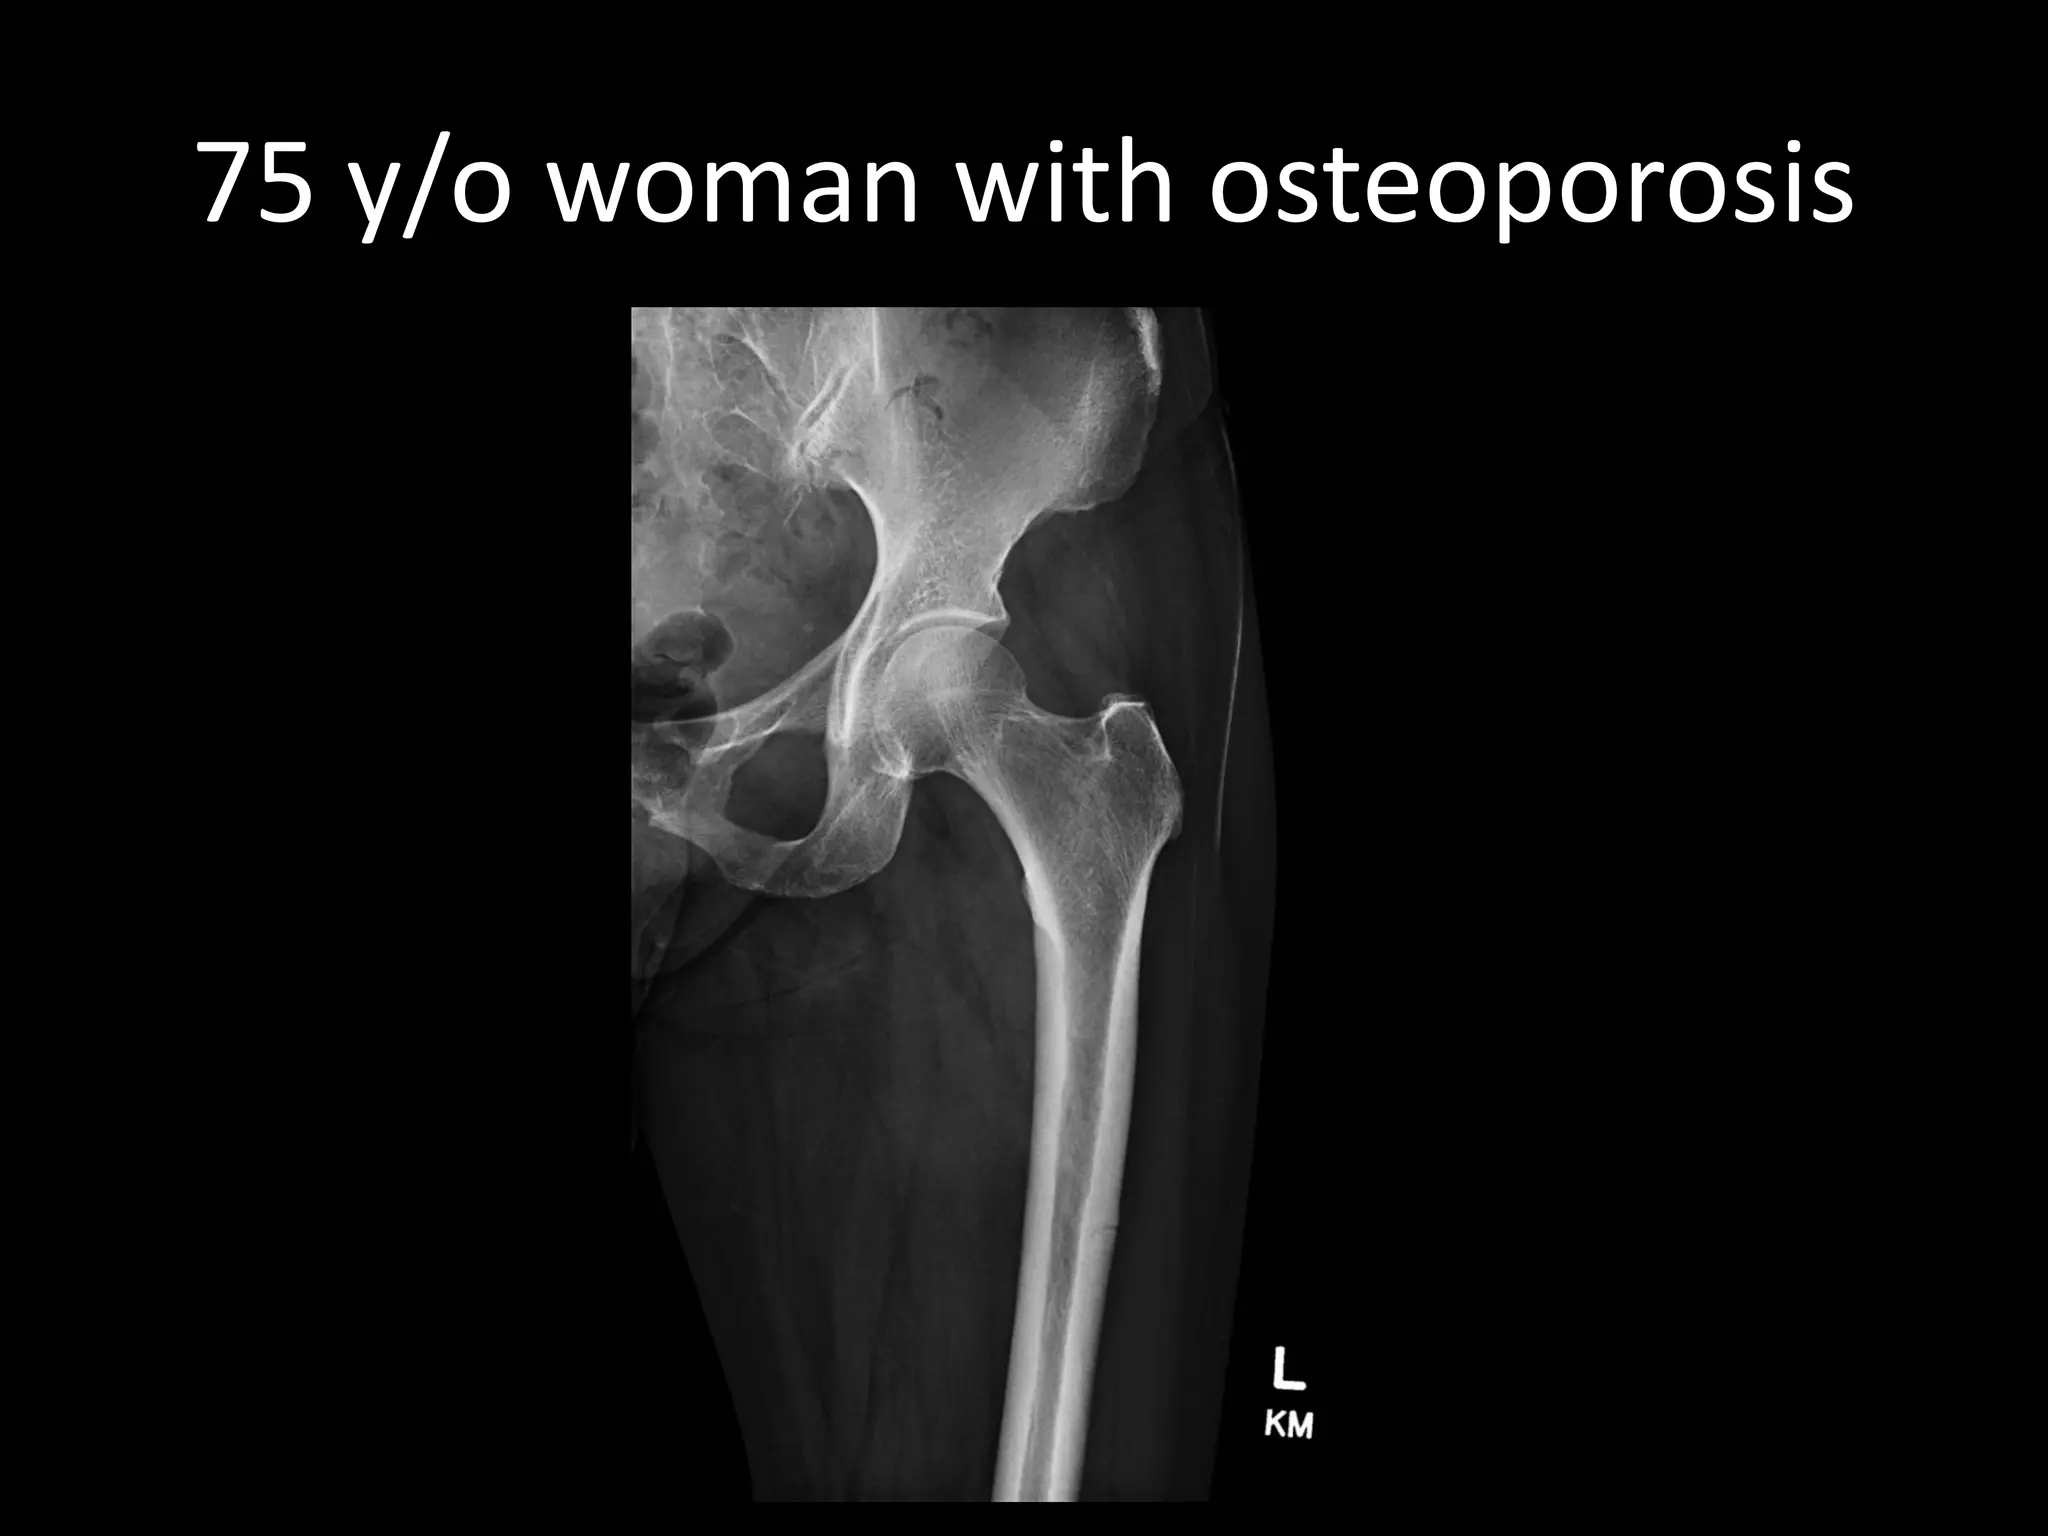

75 y/o woman with osteoporosis

•Long term use of bisphosphonate

•Can also occur without bisphosphonates

•Osteoclast oversuppression → impaired bone remodeling → accumulation of microdamage

•Decreased elasticity, increased brittleness

Atypical femoral fracture

75 y/o womanwith osteoporosis

•Long term useof bisphosphonate •Can also occur without bisphosphonates •Osteoclast oversuppression → impaired bone remodeling → accumulation of microdamage •Decreased elasticity, increased brittleness Atypical femoral fracture